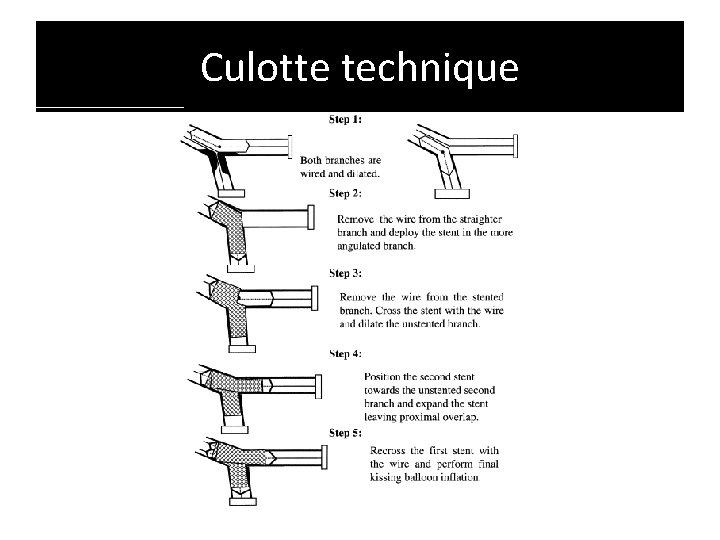

Culotte technique

� It provides near-perfect coverageof the carina &SBostium atthe expense of an excessof metal covering in proximal. MB. � Bestimmediate angiographic result &theoretically itmayguarantee a more homogeneous distribution of struts &drug. � Canbeused in all bifurcation lesions irrespective of bifurcationangle. � Open-cell stents arepreferred when the SBdiameter is >3 mm. � Disadvantages – � Complexity in the rewiring of both branches through the stentstruts, � Not advisable if both branches aredissected afterpredilatation.